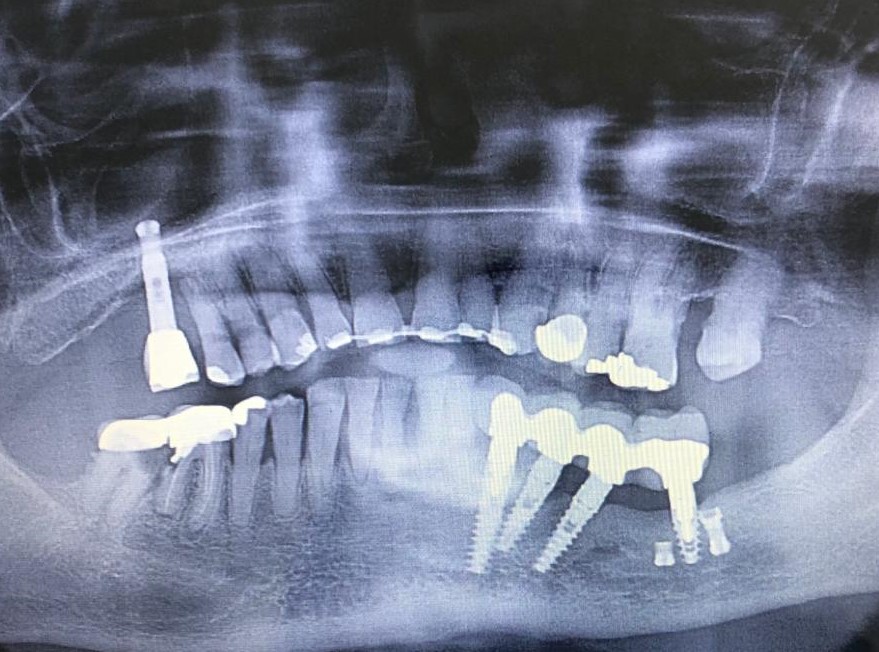

DOLOR EN PRÓTESIS SOBRE DIENTES NATURALES TALLADOS

Presentamos un nuevo caso en el que la paciente presenta un gran dolor en su prótesis antigua (15 años) sobre dientes naturales tallados en zona inferior de molares. Es una paciente muy bruxómana, se unieron dos molares tallados con dos coronas. En el caso que presentamos el molar anterior estaba endodonciado ya antes de colocar la prótesis fija, pero el molar distal no. Y éste era la causa del gran dolor. Esto es por haberse filtrado creando caries y destrucción dentaria que llegaba al nervio. En conclusión, produciendo una gran pulpitis.

Con la secuencia de imágenes se comprende muy bien la técnica quirúrgica realizada.